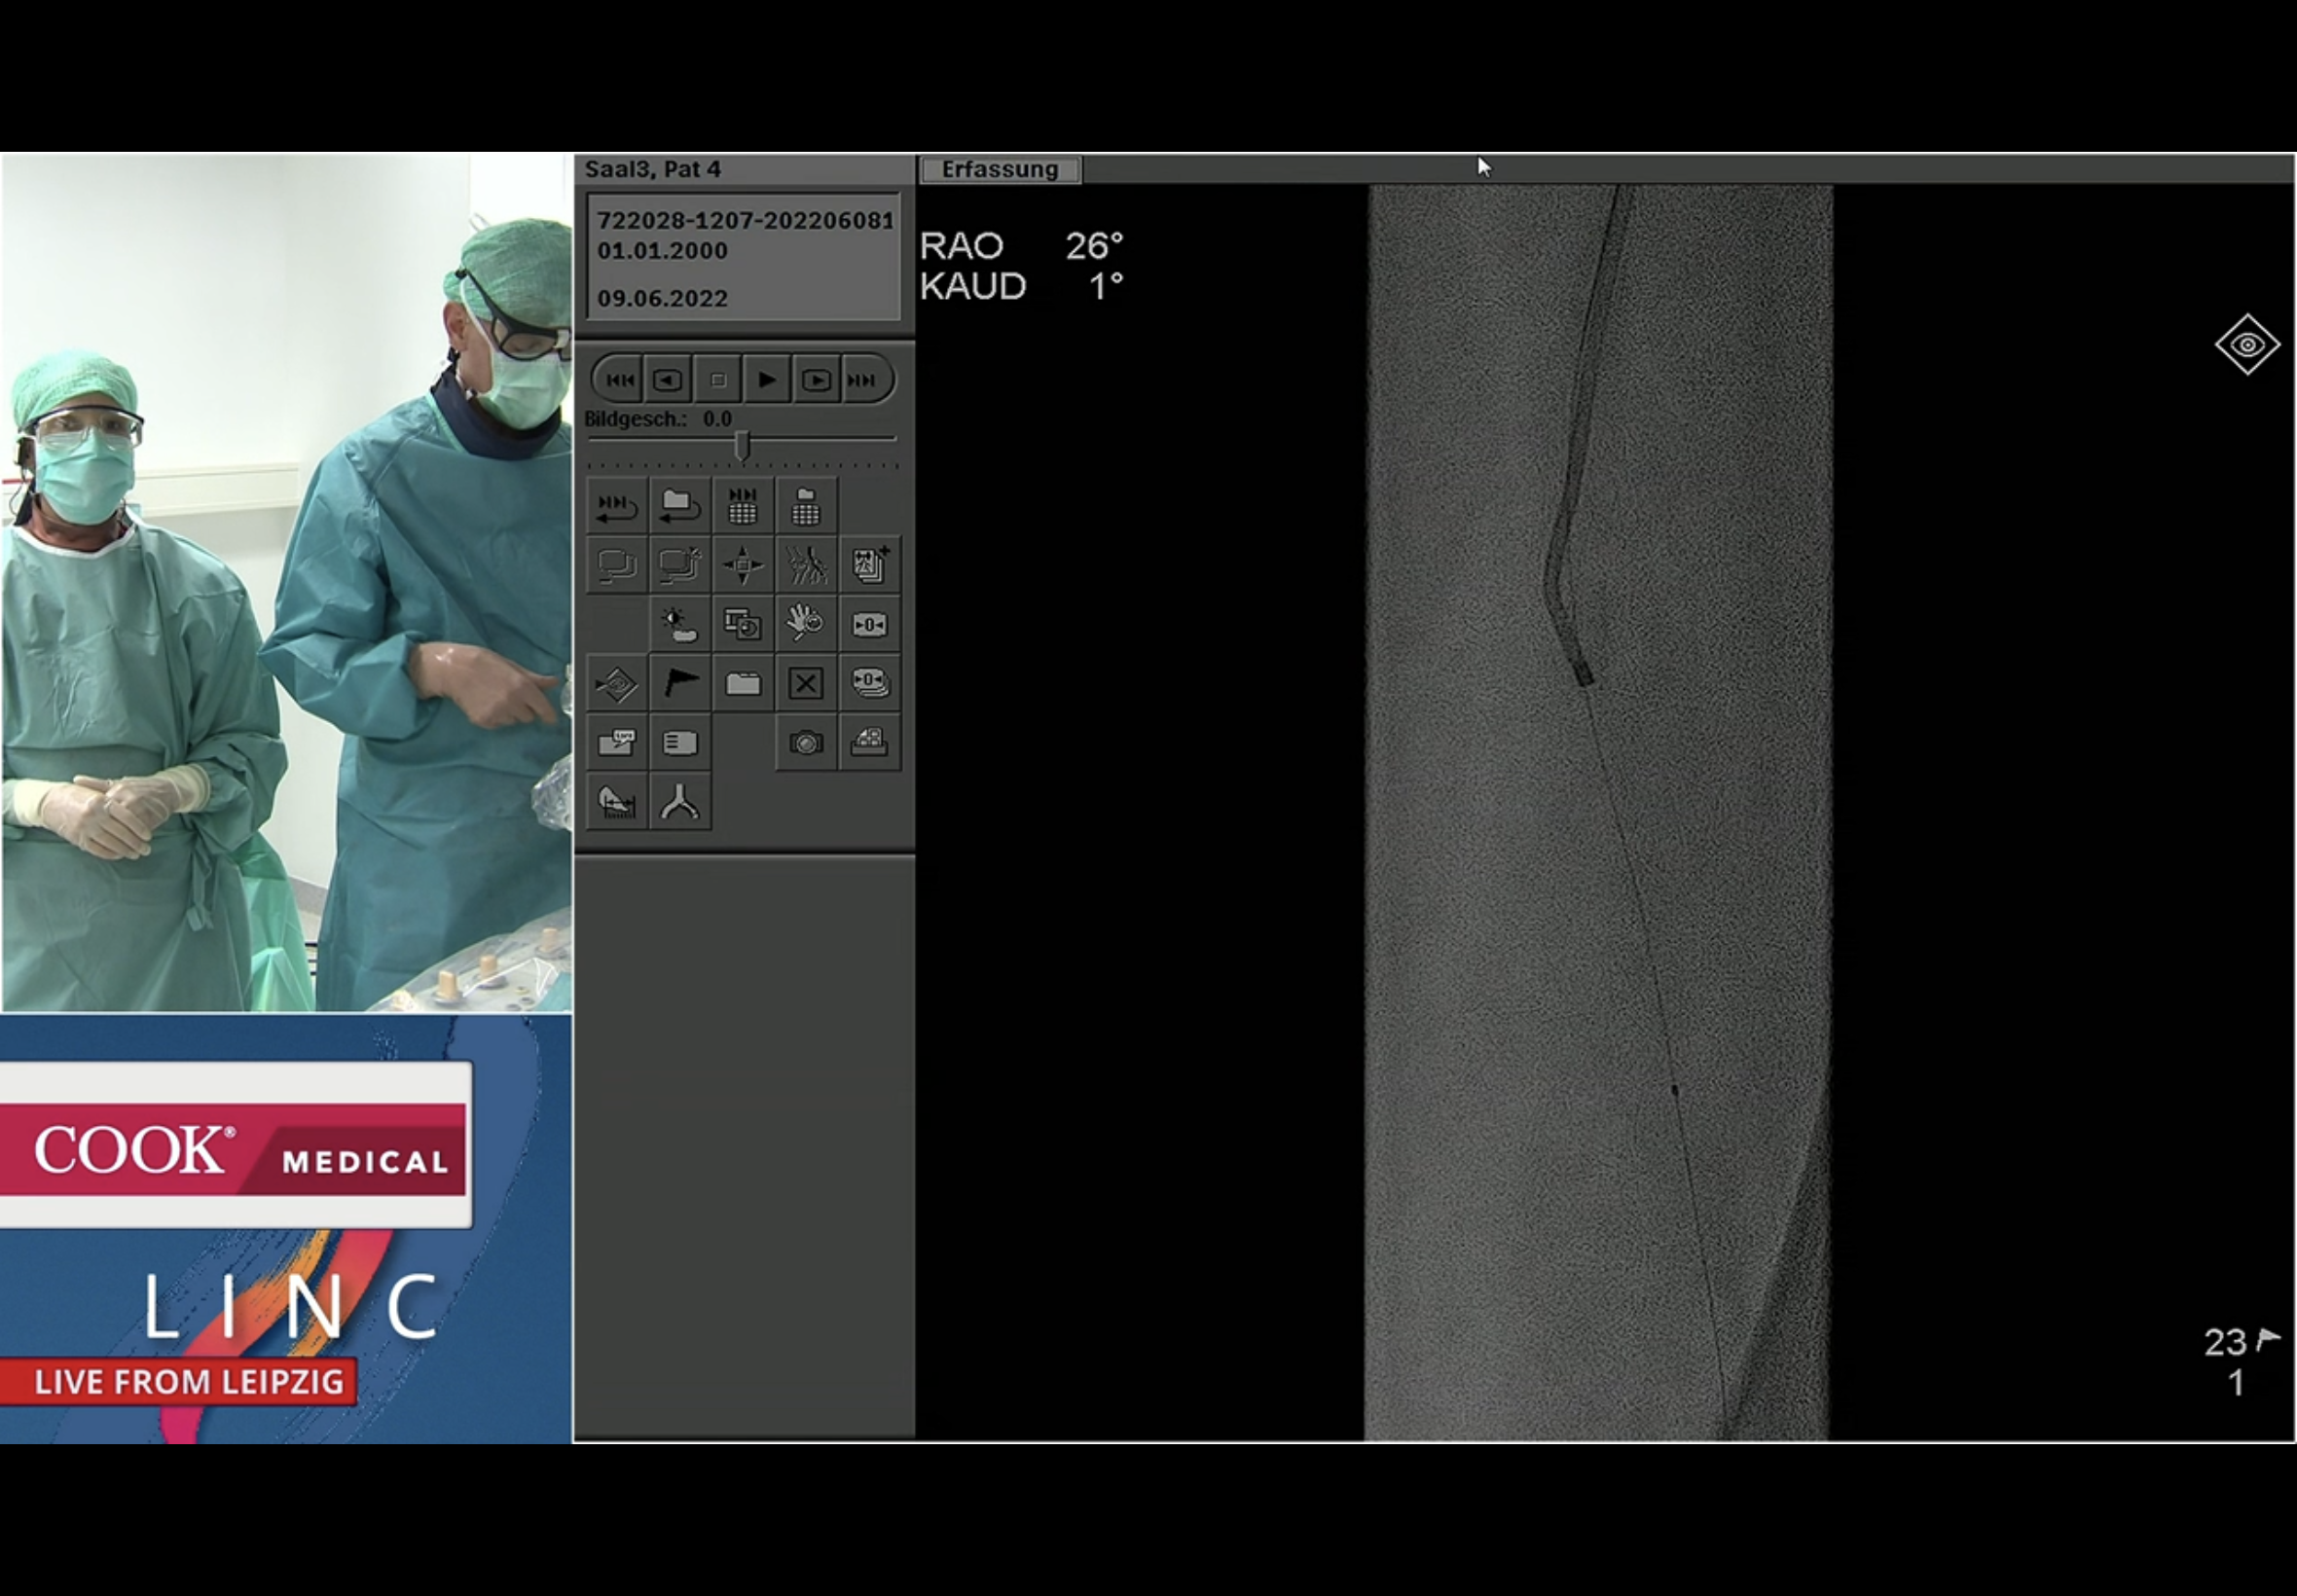

The wire going up the PeA from below first turns laterally out into a collateral; then it turns medially and Andrej susses that it may in fact have gone into the PTA origin.

So he then decided it made sense to go ahead and balloon the proximal PTA up and over from the retro PeA approach! As you do : - )